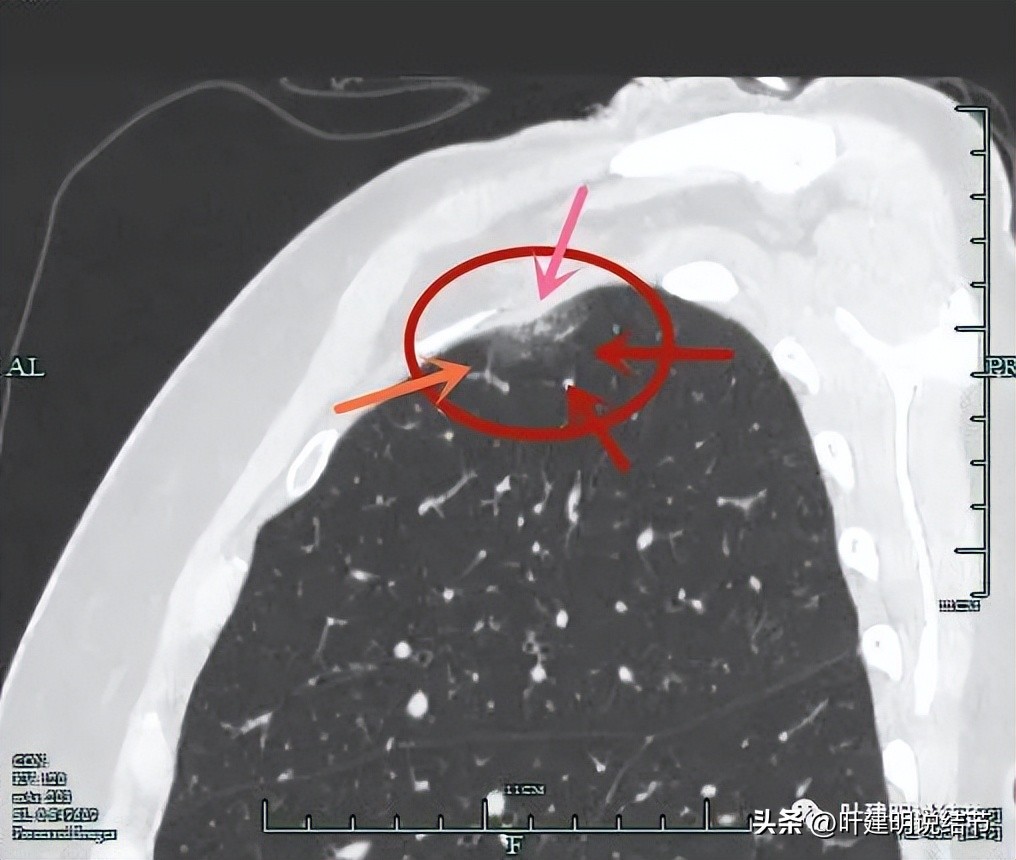

右上叶见磨玻璃密度结节,紧邻胸膜

胸膜侧似乎有偏实性成分

确实有实性成分,而且与胸壁间隙不清,而磨玻璃部分轮廓与瘤肺边界都比较清楚

病灶表面不平(砖色箭头);有实性成分(粉色箭头);连缘有毛刺(紫色箭头);整体瘤肺边界清(红色箭头)。